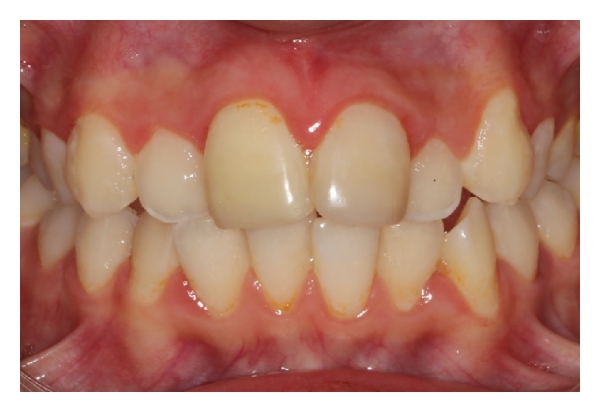

A 10-year-old boy was referred to the pediatric dental clinic after a bicycle accident that resulted in dental trauma. The avulsed tooth was not placed in any storage medium and was brought to the clinic dry 7 hours after the accident. Any concomitant systemic disease is not defined by the patient’s parents; there was no history of loss of consciousness or vomiting. On examination, no extra-oral injury was detected. The intraoral examination revealed that the maxillary right permanent central incisor (tooth 11) was avulsed (Figure 6). The left central incisor (tooth 21) showed enamel cracking and fracture. The patient had permanent dentition, with mild crowding and incisal overjet. No carious lesions were detected clinically, and his oral hygiene was fair.

Two weeks after replantation, the patient was reviewed, and no clinical or radiological evidence of pathological changes was detected. The patient was seen again four weeks after replantation, and the splinting wire was removed at this appointment. The permanent restoration of the fractured teeth crowns were completed with composite resin. At a recall visit three months later, ankylosis of the replanted tooth was observed with a percussion test. Clinical and radiographic controls were performed at six and 12 months. During the 12-month follow-up, clinical and radiographic examinations showed satisfactory functional and esthetic values for the avulsed tooth but some initial resorption and ankylosis with no infraocclusion (Figures 9 and 10). The patient will be monitored till her growth is complete and appropriate treatment will be carried out if needed.